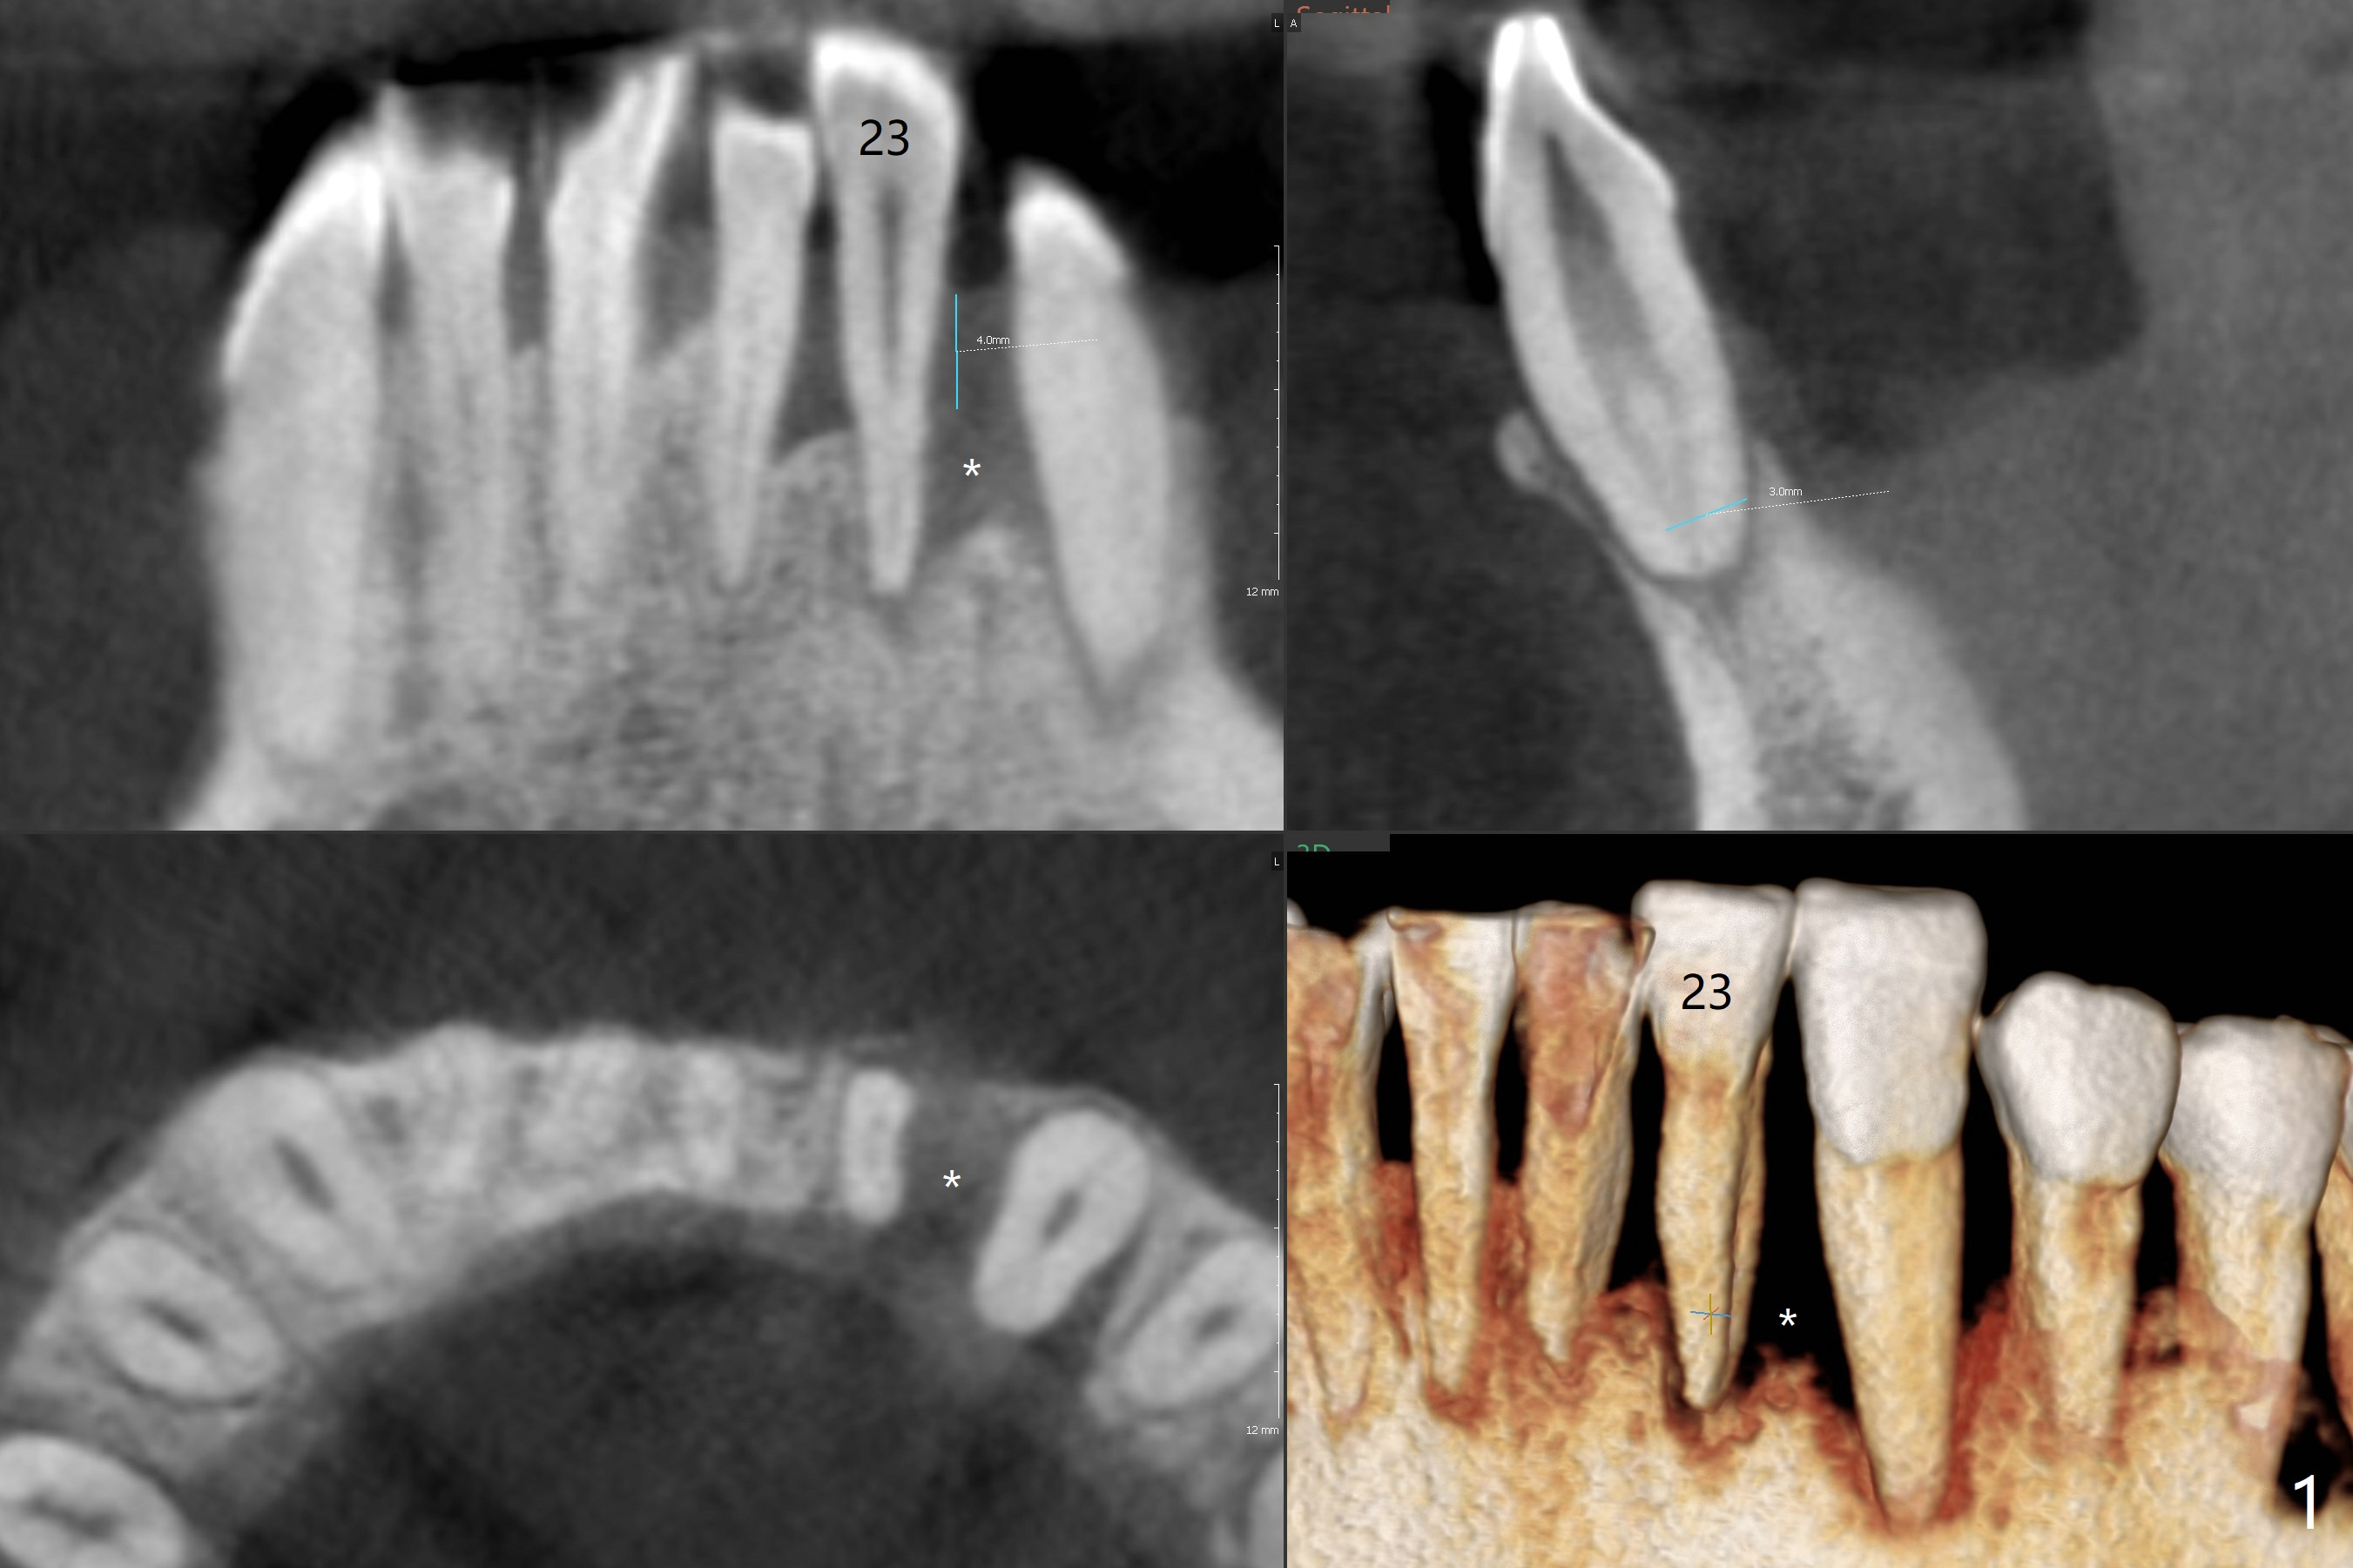

A 47-year-old man has strong desire to take care of #7 cross bite and #23 periodontitis after finishing implants at #3, 9, and 19. CBCT taken 2 years earlier shows severe bone loss around the tooth #23, especially distal (Fig.1 *). After placement of a 3 mm 1-piece implant with 4 mm cuff (because of the thick gingiva), pack bone graft between #22 and 23. Take preop photos and PAs.